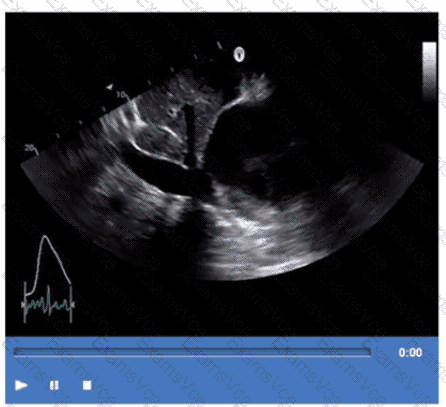

Based on this video, what is the estimated right atrial pressure in millimeters of mercury (mmHg)?